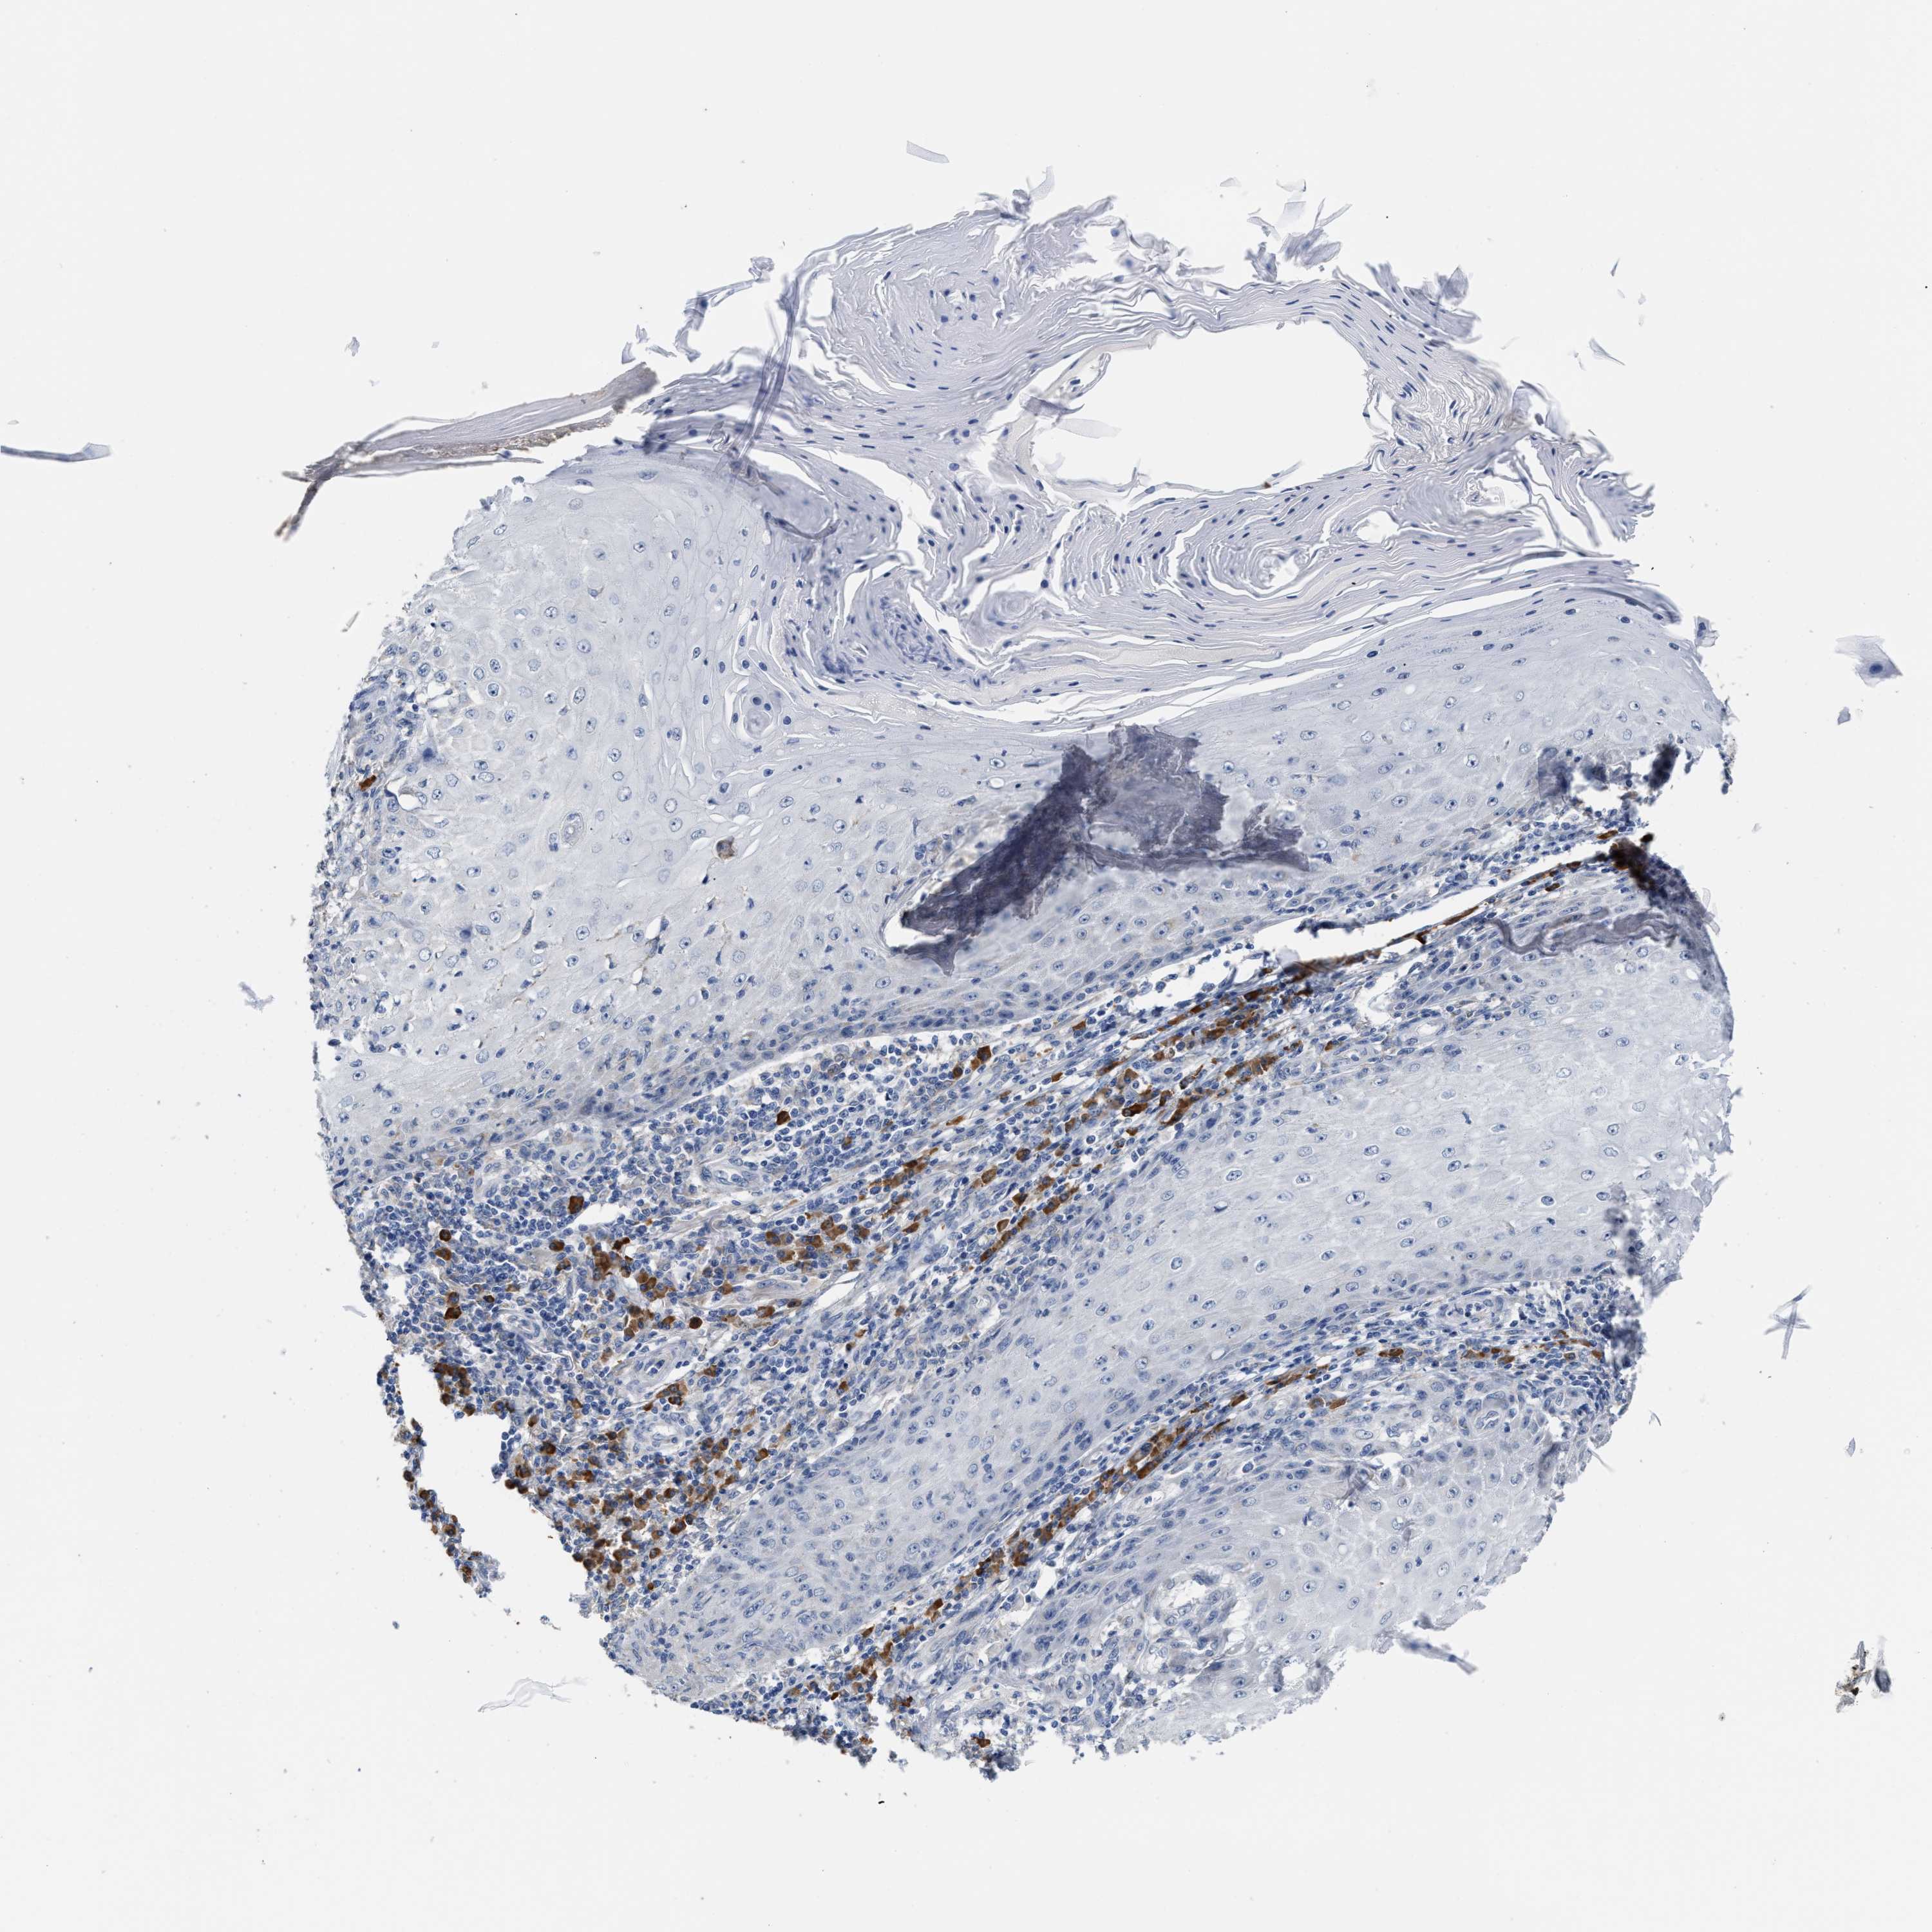

Basal cell and squamous cell cancer

SKIN CANCER - Protein expressioni

A mouse-over function shows sample information and annotation data. Click on an image to view it in a full screen mode. Samples can be filtered based on level of antibody staining by selecting one or several of the following categories: high, medium, low and not detected. The assay and annotation is described here.

Antibody stainingi

Antibody staining in the annotated cell types in the current human tissue is reported as not detected, low, medium, or high, based on conventional immunohistochemistry profiling in selected tissues. This score is based on the combination of the staining intensity and fraction of stained cells.

Each image is clickable and will lead to virtual microscopy that enables deeper exploration of all samples and also displays staining intensity scores, fraction scores and subcellular localization as well as patient and tissue information for each sample.

Antibody HPA020028

Staining

High

Medium

Low

Not detected

Intensity

Strong

Moderate

Weak

Negative

Quantity

>75%

75%-25%

<25%

None

Location

Nuclear

Cytoplasmic/membranous

Cytoplasmic/membranous,nuclear

Basal cell carcinoma

Squamous cell carcinoma, NOS

Squamous cell carcinoma, metastatic, NOS